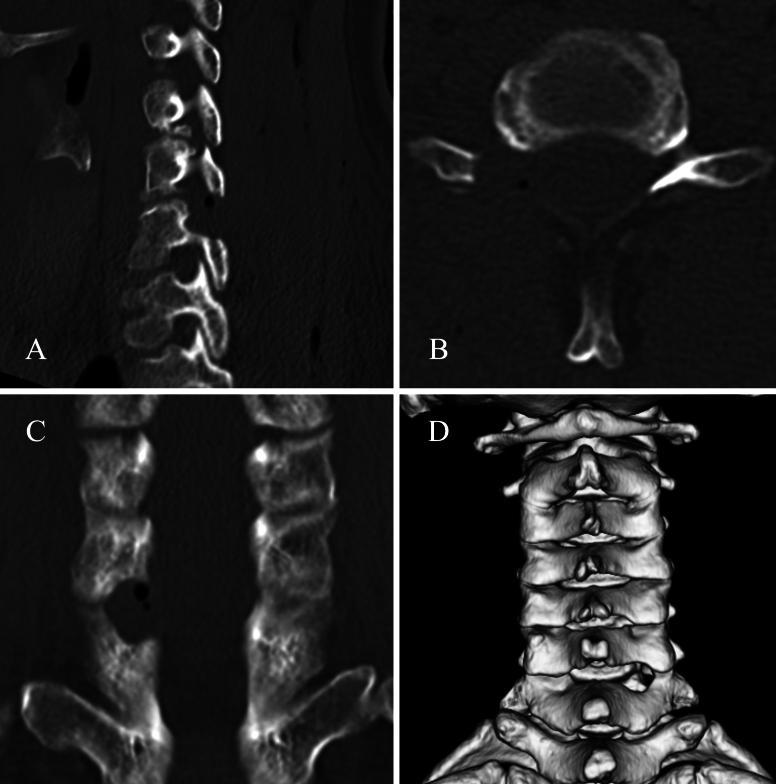

A 40-year-old female presented with painful numbness and paresis in the right upper limb. Physical examination revealed multiple radiculopathies in the C6 and C7 nerve roots. However, magnetic resonance imaging and computed tomography did not reveal any lesions explaining the right C7 radiculopathy. Furthermore, the right C6 root block injection had no effect, whereas the right C7 root block injection was extremely effective. FECF revealed a conjoined nerve root variant in the right C6-7 intervertebral foramen.

一名40岁女性出现右上肢疼痛性麻木和轻瘫。体格检查发现C6和C7神经根多处神经根病。然而,磁共振成像和计算机断层扫描未发现任何可解释右侧C7神经根病的病变。此外,右侧C6神经根阻滞注射无效,而右侧C7神经根阻滞注射极为有效。FECF显示右侧C6 - 7椎间孔存在联合神经根变异。